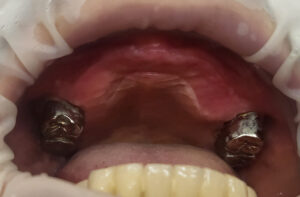

위에 남아있던 치아들 중 3개는 괜찮았었는데 이제는 4개 모두 발치를 해야 하는 상태였고, 아래도 브릿지 속 치아들이 모두 썩어서 브릿지가 흔들리고 있었어요.

드디어 수술하는 날이 되었습니다. 보철을 제거하고 상태가 좋지 않은 치아들은 모두 제거하고 남아있는 뼈를 최대한 이용해서 뼈이식과 함께 임플란트를 식립했습니다.

위 9개, 아래 12개 식립을 했고 위에는 6개 아래는 8개에 지대주를 연결해서 수술당일 임시치아를 적용해서 즉시하중 전체임플란트 치료를 했습니다.